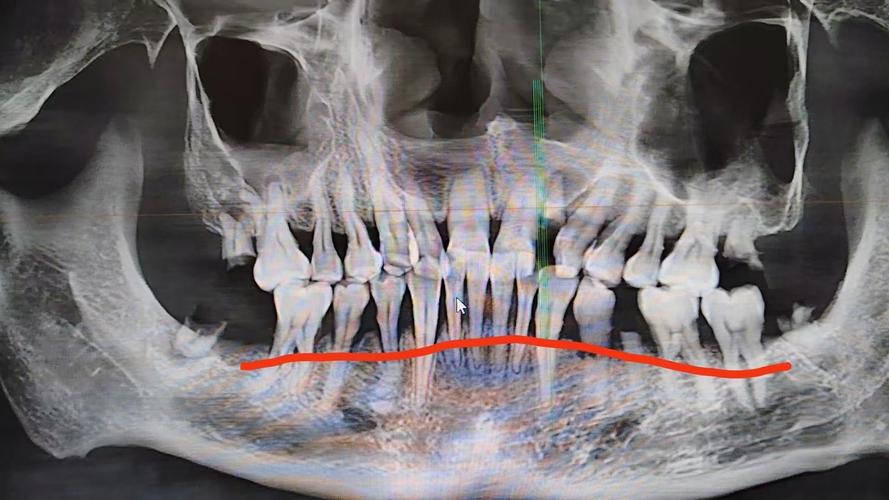

牙槽骨吸收在X光片(主要是根尖片或曲面断层片)上通常表现为以下特征:

- 最直观的表现: X光片上可以看到牙齿根尖周围的牙槽骨(硬骨板)的高度比治疗前或健康邻牙低。

- 骨皮质变薄或模糊: 牙根周围的白色致密骨线(牙槽骨的骨皮质)变得不清晰、变薄甚至中断。

- 牙槽嵴顶高度下降: 牙龈缘对应位置的牙槽骨顶部(牙槽嵴顶)位置降低。

- 骨小梁结构稀疏: 牙槽骨内部的骨小梁(网状结构)变得稀疏、排列紊乱,透光度增加(在X光片上看起来更“黑”一些)。

- 骨透射影: 在吸收严重的区域,可能看到更明显的黑色透射影,表示骨量减少。

- 增宽: 在牙槽骨吸收区域,牙齿与牙槽骨之间的牙周膜间隙可能暂时性或持续性增宽,这通常表示牙齿在移动或受到轻微创伤,是正畸过程中常见的现象,但持续增宽或异常增宽可能提示问题。

- 模糊: 吸收区域的牙周膜间隙边界可能变得模糊不清。

(图片来源网络,侵删)- 牙根吸收: 虽然牙根吸收和牙槽骨吸收是两个概念,但严重的牙槽骨吸收有时会伴随或导致牙根吸收,X光片上可见牙根长度缩短或形态不规则。

骨皮质中断: 牙根外侧的骨皮质线出现中断或消失。

- X光片类型: 根尖片能更清晰地显示单颗牙齿周围的牙槽骨细节,是评估牙槽骨吸收最常用的影像学方法,曲面断层片可以同时显示全口牙槽骨情况,但单颗牙齿的细节不如根尖片清晰。